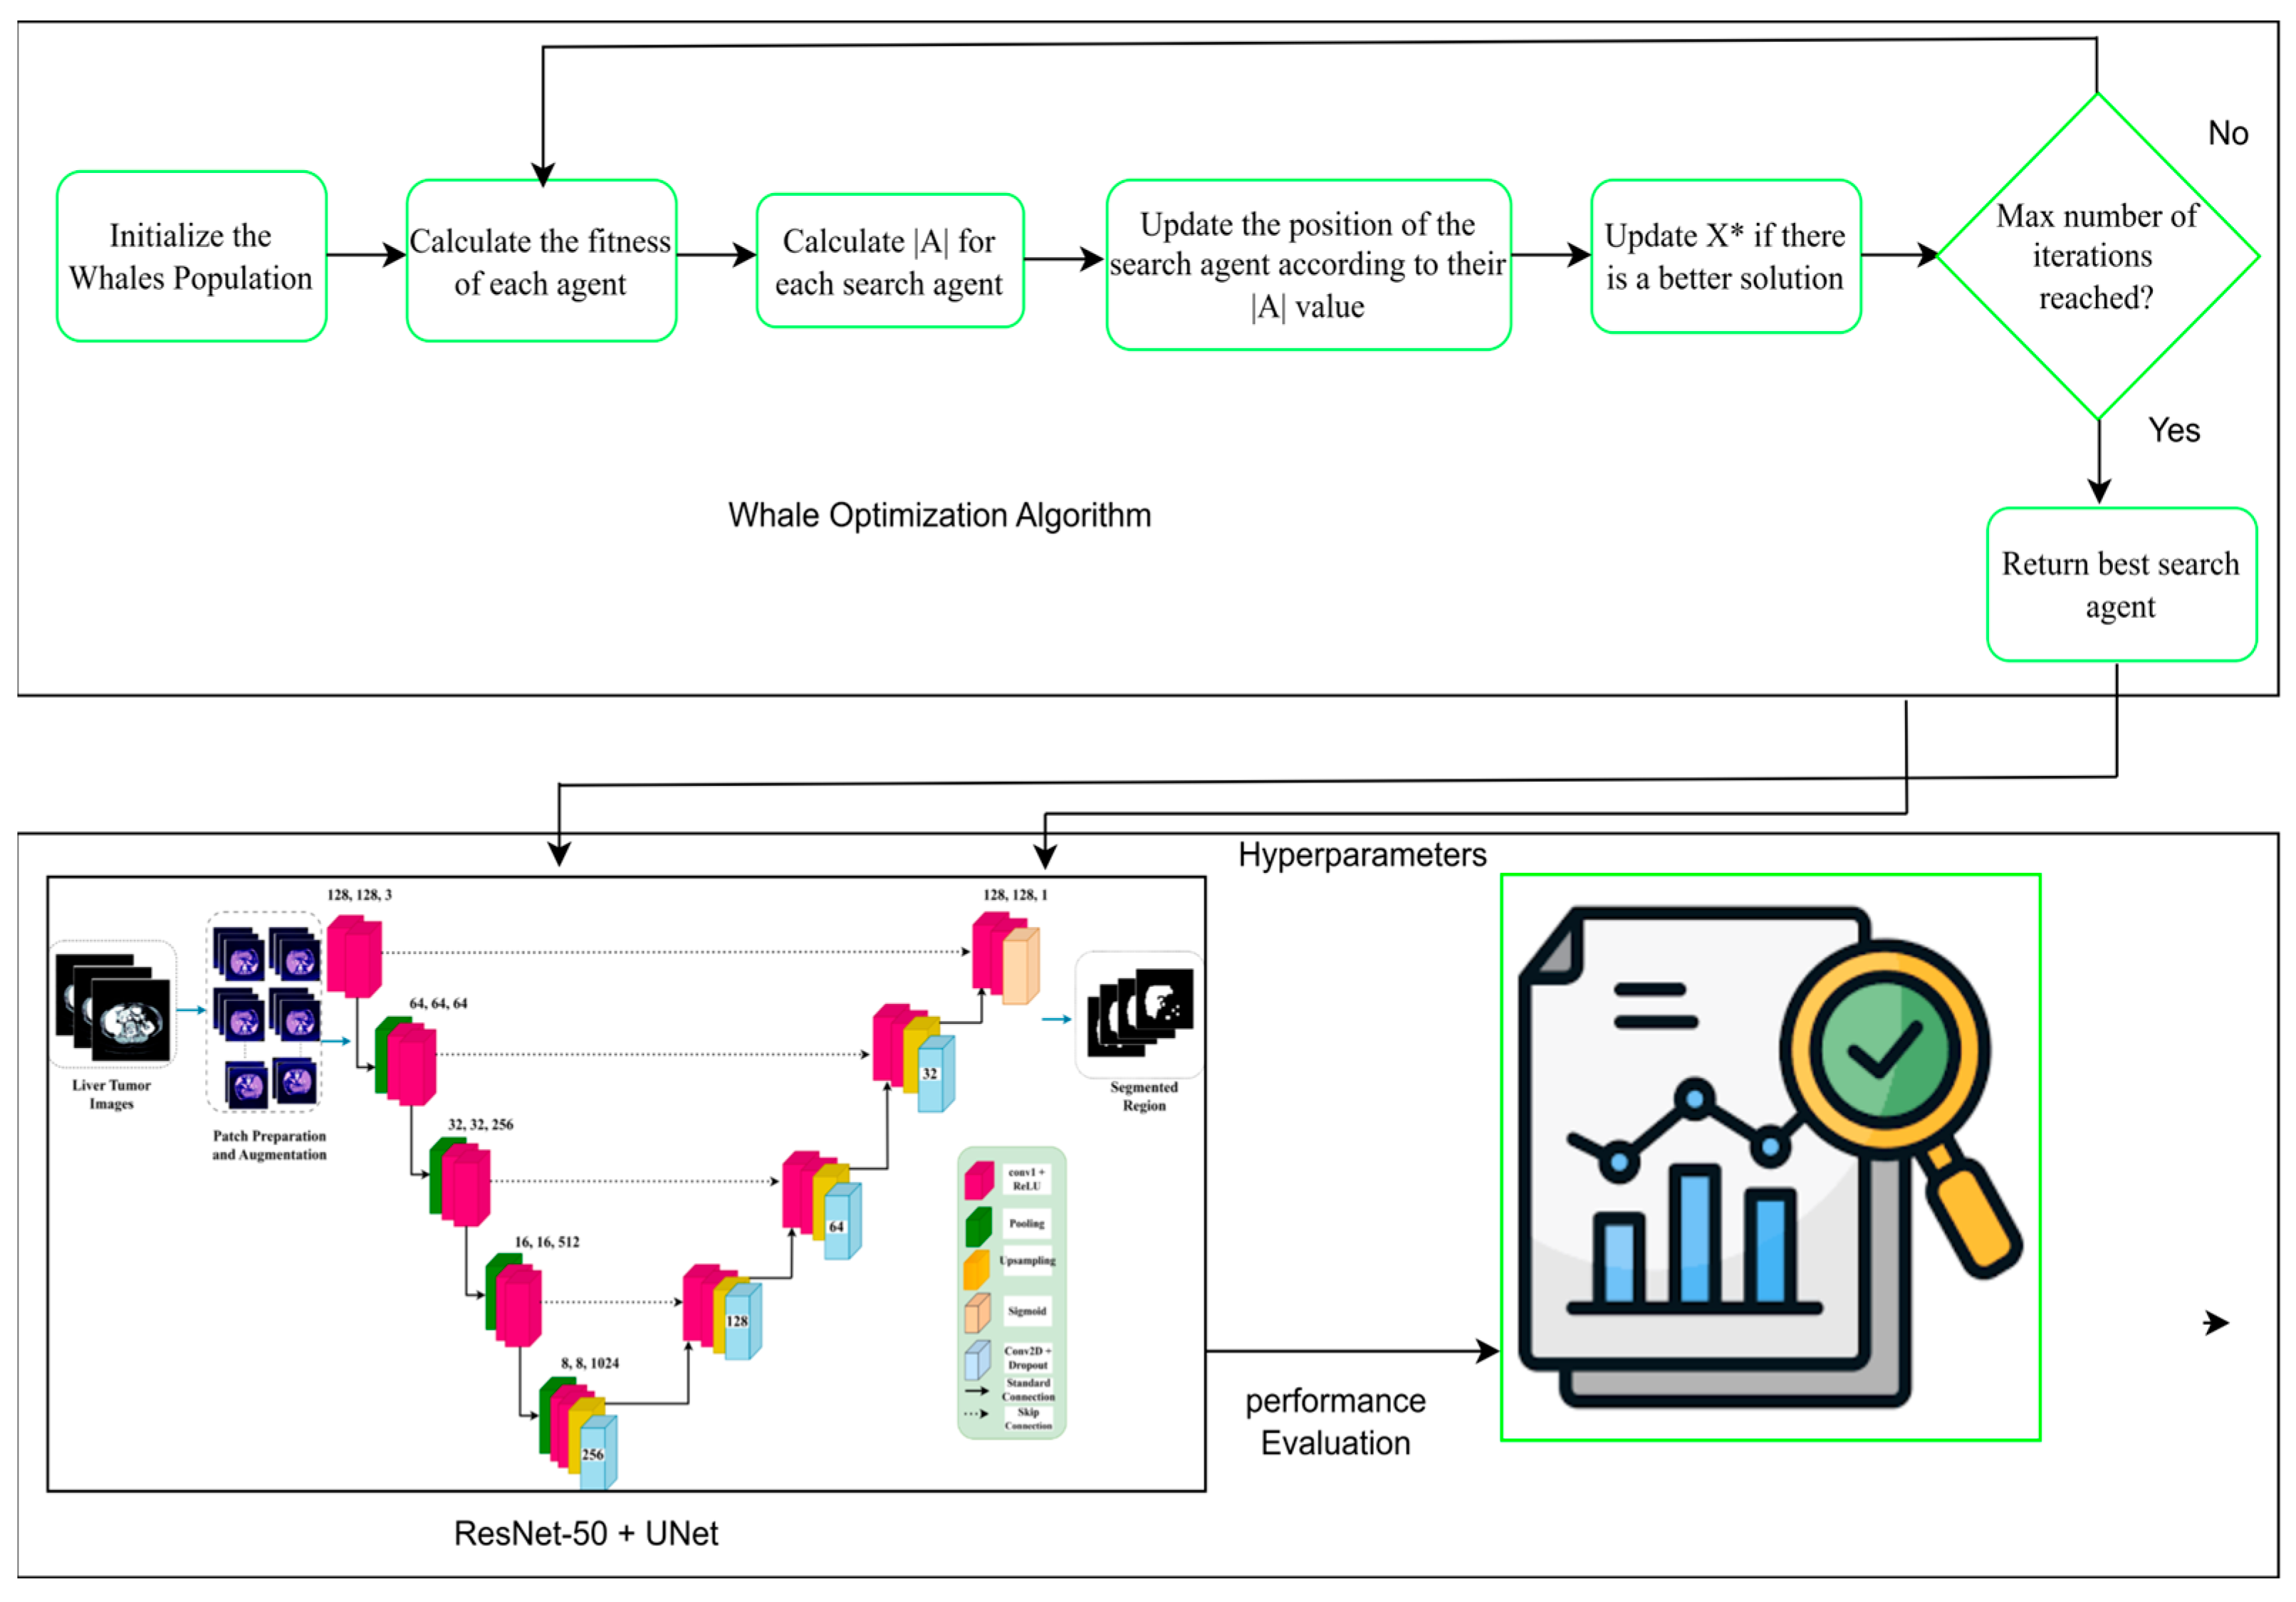

- We propose a novel hybrid optimization-segmentation framework called LiTs-Res-Unet + WOA, which integrates the Whale Optimization Algorithm (WOA) with a UNet-based architecture to automatically and adaptively tune the hyperparameters required for liver and tumor segmentation.

- Unlike prior studies that apply WOA to optimize a single parameter, we propose a closed-loop optimization framework in which WOA tunes a set of interdependent hyperparameters (learning rate, dropout rate, batch size) dynamically during training. This introduces a meta-optimization layer that is adaptive to the changing loss landscape of the ResNet-50–U-Net model.

- The inner level updates the network weights using backpropagation, and the outer level optimizes a population-based hyperparameter search using WOA by the validation Dice score. The convergence of validation performance shows that the hyperparameter optimization (HO) by the WOA outperforms the grid search and the Bayesian optimization methods because it achieves a better exploration–exploitation trade-off.

3.4. Swarm-Based Whale Optimization Algorithm (WOA)

3.4.1. Motivation from Nature

3.4.2. Exploration and Exploitation Phases

- Exploration: This process iteratively traverses the search dimensions in search of the global optimum. During this phase, whales move randomly to search for unvisited regions. The search is guided by the position of the best solution found so far, allowing the algorithm to escape local optima.

- Exploitation: This phase focuses on refining the search around the best solution detected. Whales use the shrinking (enclosing) mechanism along with the spiral path, updating their position by considering the spiral trajectory, which converges more effectively to the global optimum.

3.5. Proposed U-Net Segmentation with WOA

3.5.1. Hyperparameter Tuning with Whale Optimization Algorithm

3.5.2. Mathematical Formulation of WOA-Segmentation Coupling

3.6. ResNet-50 + U-Net

3.6.1. Encoder

3.6.2. Decoder

3.6.3. Bottleneck

3.6.4. ResNet-50 Backbone